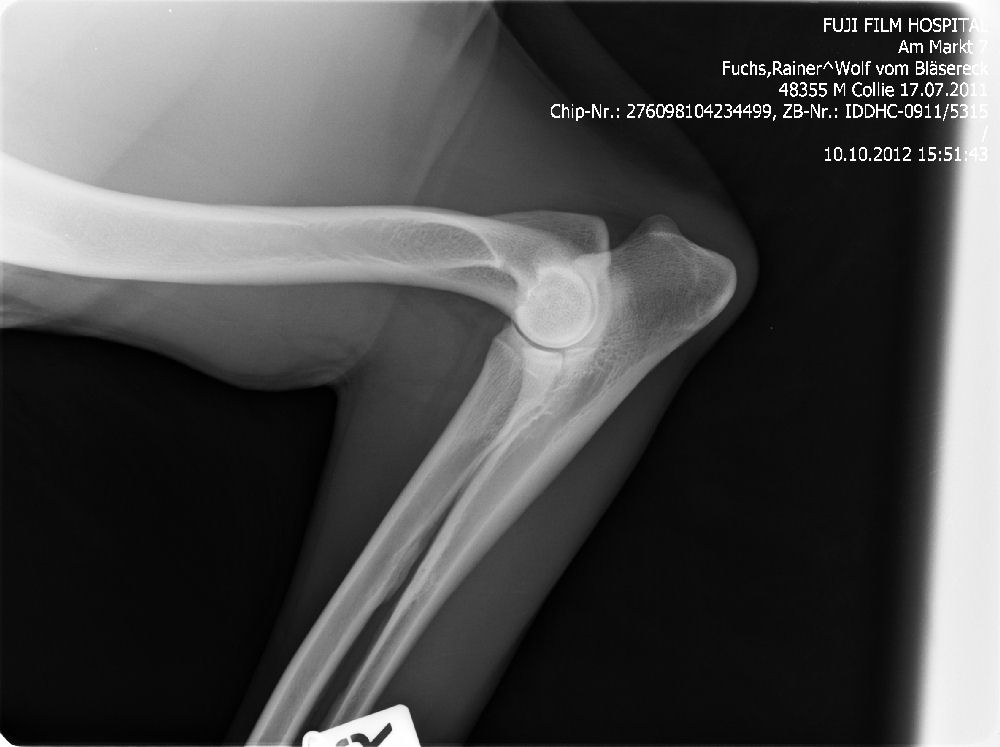

Ab dem Jahr 2008 wird nur noch Digitales Röntgen durchgeführt, da wir auch hier wieder führend und transparent sind, zeigen wir gern die Röntgenbilder ! Bei Züchtern, die dies nicht tun, haben Sie weniger Sicherheit !